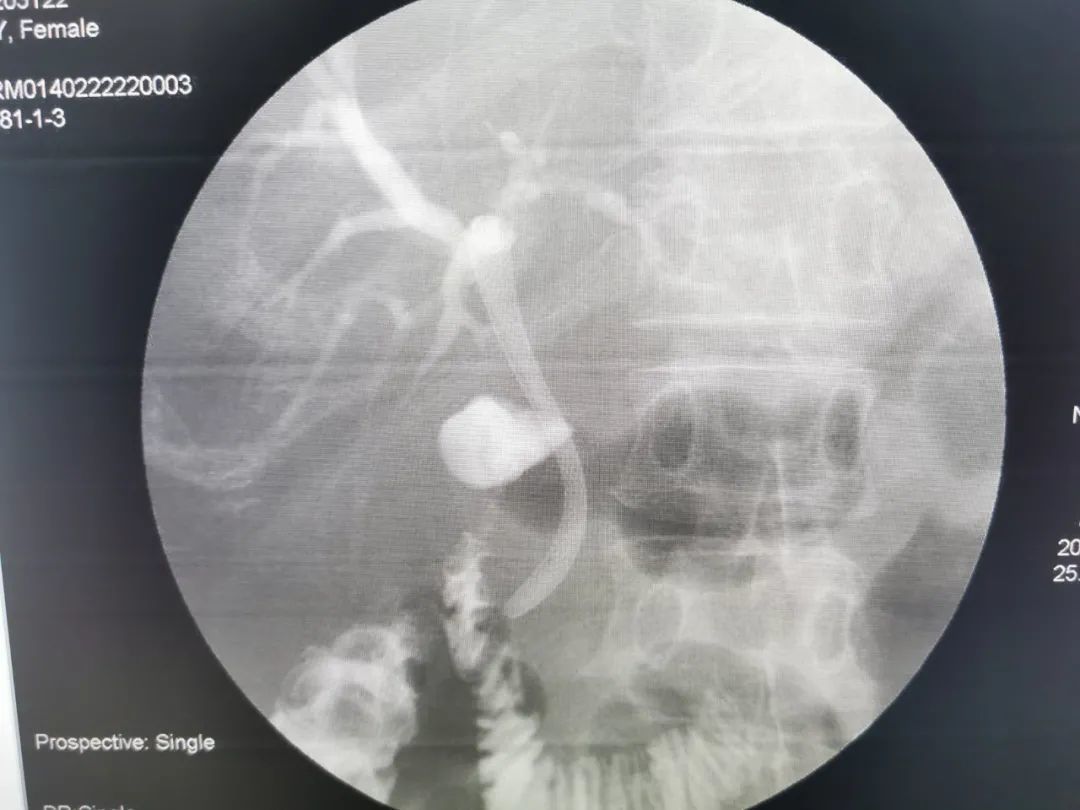

术后

治疗:为患者行胆管内支架植入术。术中经原胆道外引流注入造影剂示肝内胆管扩张,置入超滑导丝交换出原引流管并置入鞘管、造影导管,超滑导丝缓慢开通闭塞段,造影示:胆总管上段、肝总管、肝左、右胆管闭塞。超滑导丝引导下将8mm*60mm胆道支架置入胆管闭塞段,见支架扩张良好,造影剂通过顺利,再将造影导管置于支架内,固定引流管。术后拔除导管,经皮植入胆道支架,恢复解剖通道,患者黄疸、腹痛等症状明显减轻。